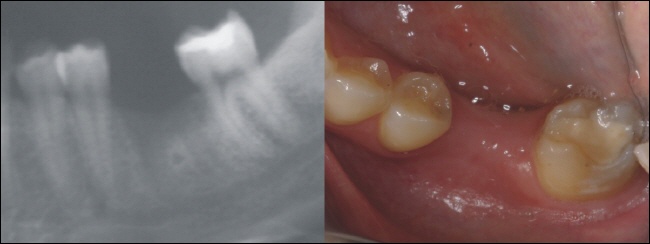

Das Röntgenbild links zeigt den perfekten Sitz der Implantatkrone. Die Lücke ist ohne weitere Schäden an Nachbarzähnen stabil versorgt. Für den Patienten ist die Implantatkrone nun gar nicht mehr zu erkennen und der Zahn im Ganzen nach dem Vorbild der Natur wiederhergestellt.

Der gelbe Pfeil zeigt auf dem Bild rechts, wo sich die Implantatkrone in der Zahnreihe „versteckt“.